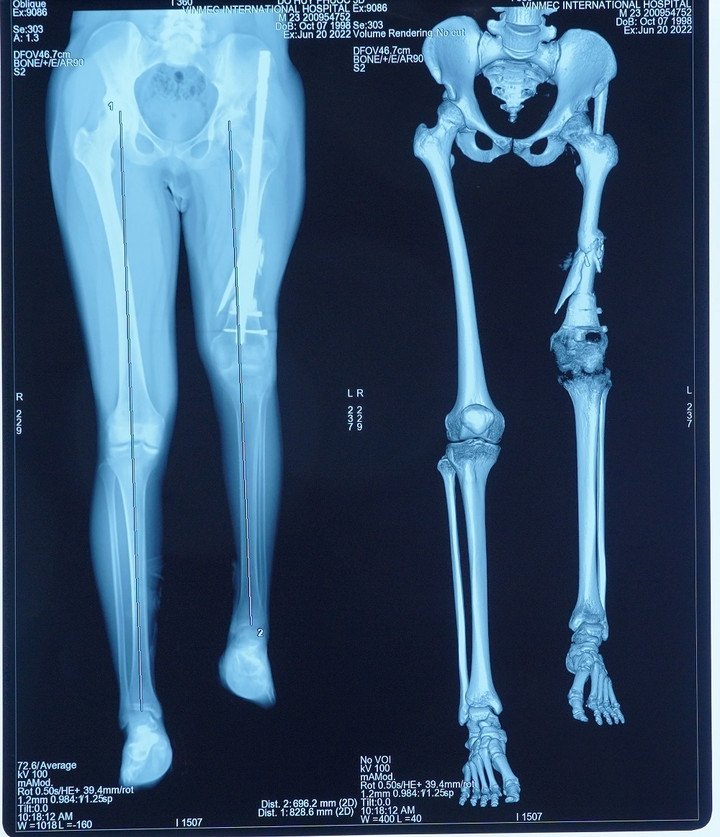

Các bệnh nhân kéo dài chân thông thường (kéo cả 2 chân) sẽ được kết hợp kéo cả 2 xương trên và dưới đầu gối là xương đùi và xương chày. Trường hợp của anh P. nan giải hơn khi chỉ kéo dài một chân trái. Cái khó là làm sao để tránh tình trạng 2 đầu gối bên cao bên thấp. Chưa hết, vấn đề cần khắc phục chính là ở xương đùi ngắn và phần mềm tại đây co rút. Điều trị đúng nguyên nhân rất quan trọng và cũng là thách thức khi kéo dài một khoảng cách lớn ở riêng phần đùi.

Sau nhiều lần thăm khám, hội chẩn, GS. Dũng và ekip đã đi đến phác đồ điều trị 2 giai đoạn: Gỡ dính và kéo phần cơ đang co rút ra tối đa có thể, sau đó thực hiện phẫu thuật ghép xương đùi và đầu gối nhân tạo bằng vật liệu y sinh.

Toàn bộ kích thước, trọng lượng xương nhân tạo sẽ được tính toán bằng công nghệ 3D để đảm bảo gần với chân lành nhất. Bệnh nhân đã 24 tuổi và ổn định chiều cao nên không lo bị chênh lệch chi và tránh nguy cơ gãy xương lần nữa, như vậy sẽ đi lại được bình thường.

Phương pháp này đã thực sự mang lại cuộc sống mới cho bệnh nhân sau khi khắc phục được độ chênh lệch giữa 2 chân lên tới 13cm.